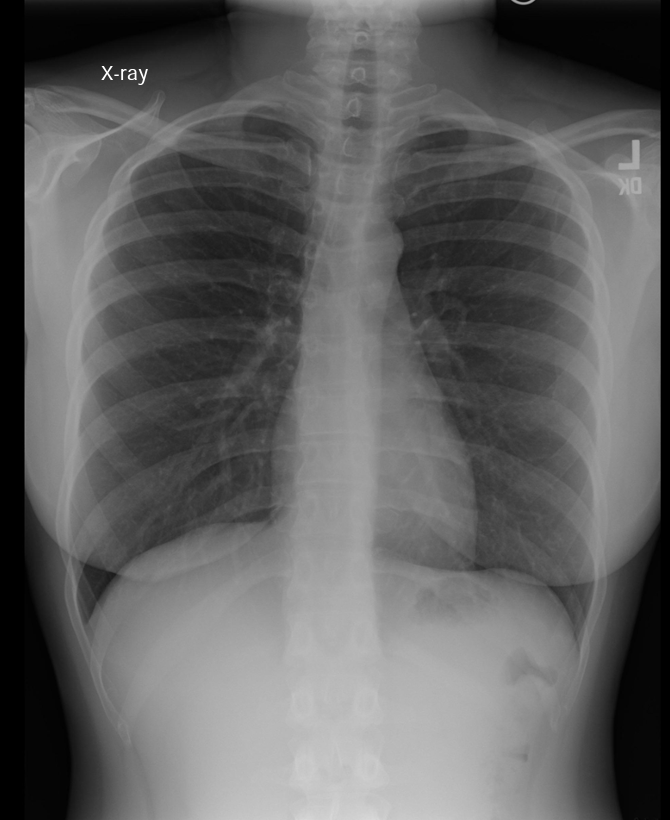

Identify Lungs, heart (if you can the different parts too), aorta, and mediastinum on chest XRay

image

Which side of the diaphragm should be higher on imaging?

The right side due to position of liver.